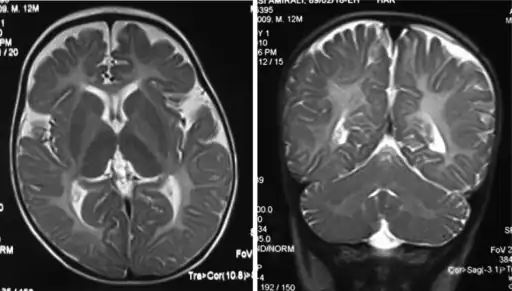

The diagnosis of Pelizaeus–Merzbacher disease is often first suggested after identification by magnetic resonance imaging of abnormal white matter (high T2 signal intensity, i.e. T2 lengthening) throughout the brain, which is typically evident by about 1 year of age, but more subtle abnormalities should be evident during infancy.

Iso intensity in bilateral periventricular deep white matter -

Left- MRI,abnormal high signal internal capsule,Right MRI,high signal white matter of cerebellum